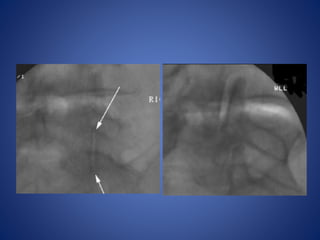

Lumbar Facet

Postero-lateral approach

Direct posterior approach

Facet Joint Capacity

Right L5–S1 facet injection with

guided fluoroscopy

Right L5–S1 facetinjection with guided fluoroscopy